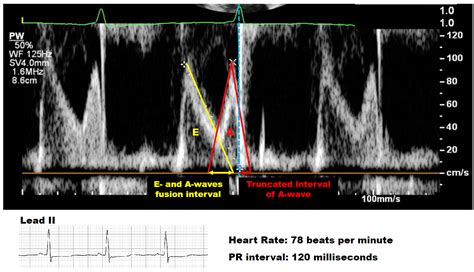

The PR interval is a fundamental component of the ECG, typically measured in milliseconds (ms). It reflects the time it takes for an electrical impulse to travel from the sinoatrial node (SA node) through the atria, the atrioventricular node (AV node), and into the ventricles. The normal range for the PR interval is between 120 ms and 200 ms. A prolonged PR interval is generally defined as greater than 200 ms.

• Echocardiography: This imaging technique can assess the structure and function of the heart, helping to identify any underlying cardiac abnormalities.